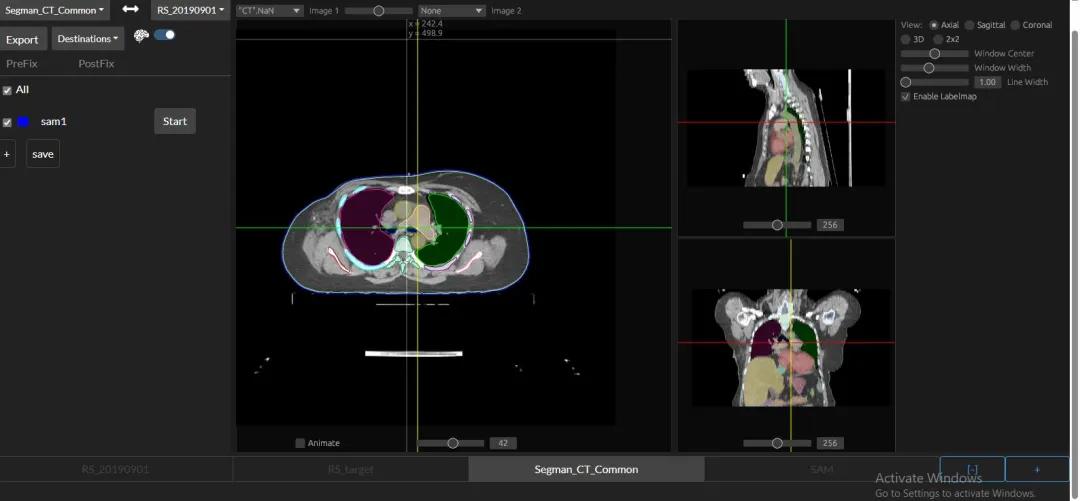

于是,在参数有限的情况下,通过将识别步骤拆分成三个不同的网络阶段,就可以降低每个步骤的认知负荷,使识别过程更加有序和精确。

具体来说,在第一阶段,PANDA会使用nnU-Net模型——一种特定的深度学习架构,精确地识别和分割出胰腺的区域。就相当于用画笔勾勒出胰腺的轮廓。

在第二阶段,一旦胰腺区域被定位和分割出来,PANDA的联合分割和分类网络,就会判断这些区域是异常的还是正常的,如果异常,就要找出相应的病变区域。

第三阶段(Stage 3)- 病变亚型分类:在检测到病变之后,这个阶段的目标是对这些病变进行更细致的分类,比如区分不同类型的肿瘤或病变。

每个阶段的专注学习,就像在逐步调整“眼镜”的焦距,让大脑(AI模型)能够更清晰地看到并理解每一个细节。